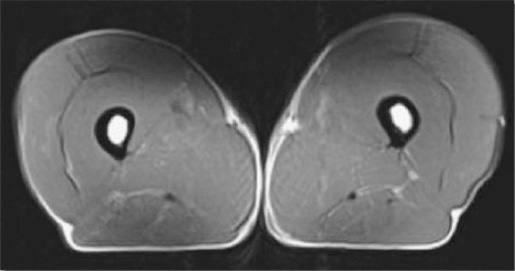

Xin cảm ơn sự đồng ý của tạp chí Physician and Sportsmedicine, Berwyn, PA cho phép tái xuất bản các hình ảnh trên trang này từ bài viết “Tập luyện kéo dài giúp duy trì khối lượng cơ bắp ở các vận động viên lớn tuổi” của tác giả Wroblewski A.P. (đồng tác giả chính), Amati (đồng tác giả chính), Smiley M.A., Goodpaster B., Wright V. từ tạp chí Physician and Sportsmedicine, 2011. Sử dụng với sự cho phép của tạp chí Physician and Sportsmedicine, Berwyn, PA.